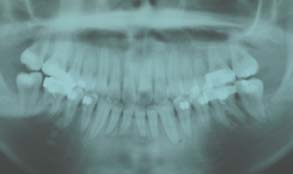

治療後

上下顎の前突感改善のため第一小臼歯の抜歯を行い最終排列を行いました。